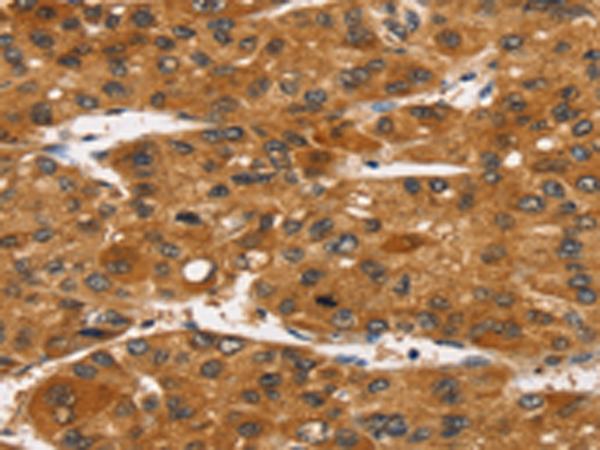

IHC positive control: |

Human liver cancer |

IHC Recommend dilution: |

25-100 |